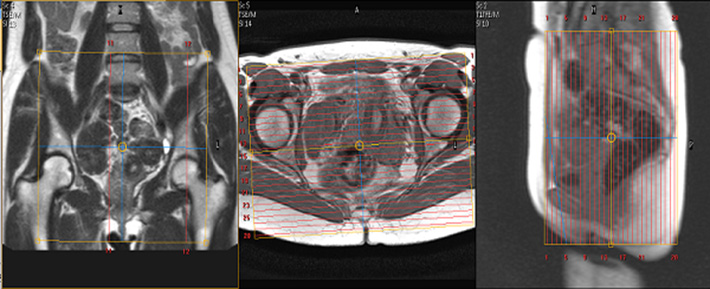

Plan the big fov coronal slices on the sagittal plane. Interpretation of mri findings the level of the pelvic floor on dynamic mri can be demarcated radiologically on the midsagittal image using the pubococcygeal line as described by yang et al. Studies have shown that dynamic pelvic mri is more sensitive than physical examination making it the gold standard for diagnosing pelvic floor disorders. Suggested protocol for dynamic mri of pelvic floor dysfunction.

An appropriate angle must be given in the axial plane parallel to the right and left hip joint. 7 high temporal resolution and excellent contrast make it well suited for evaluation of organ movement. For all pelvic mri studies except the bladder protocol or the mr urogram. Diagnostic and biopsies breast imaging protocols currently applied in our mri section.

Angle the position block parallel to the lumbar spine. Please have the patient void their bladder prior to exam to improve image quality. For dynamic mri of the pelvic floor use steady state imaging sequences.